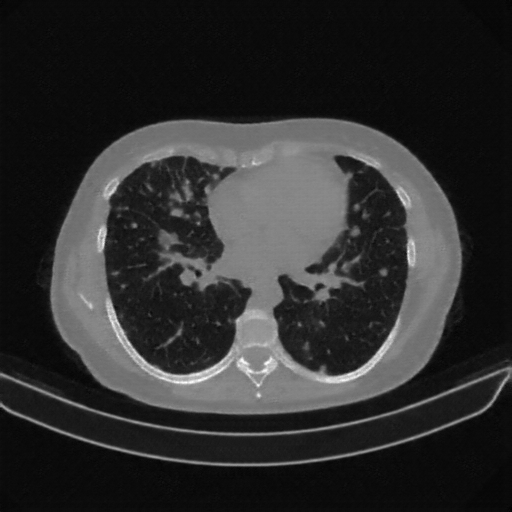

Slice 70 Targeting Evaluation

Slice: Slice_70

Conversion: NATIVE β†’ VENOUS

Targeted Slice 70 - Lung Window Analysis (Generated vs Real Venous)

0.728

Lung SSIM

109.0

Lung RMSE

48.5

Lung MAE

Reconstructed NATIVE CT scan (cycle consistency)

No window - Raw intensity values

Lung window (WL -600, WW 1500 β†’ Low βˆ’1350, High +150)

Mediastinum window (WL 40, WW 400 β†’ Low βˆ’160, High +240)